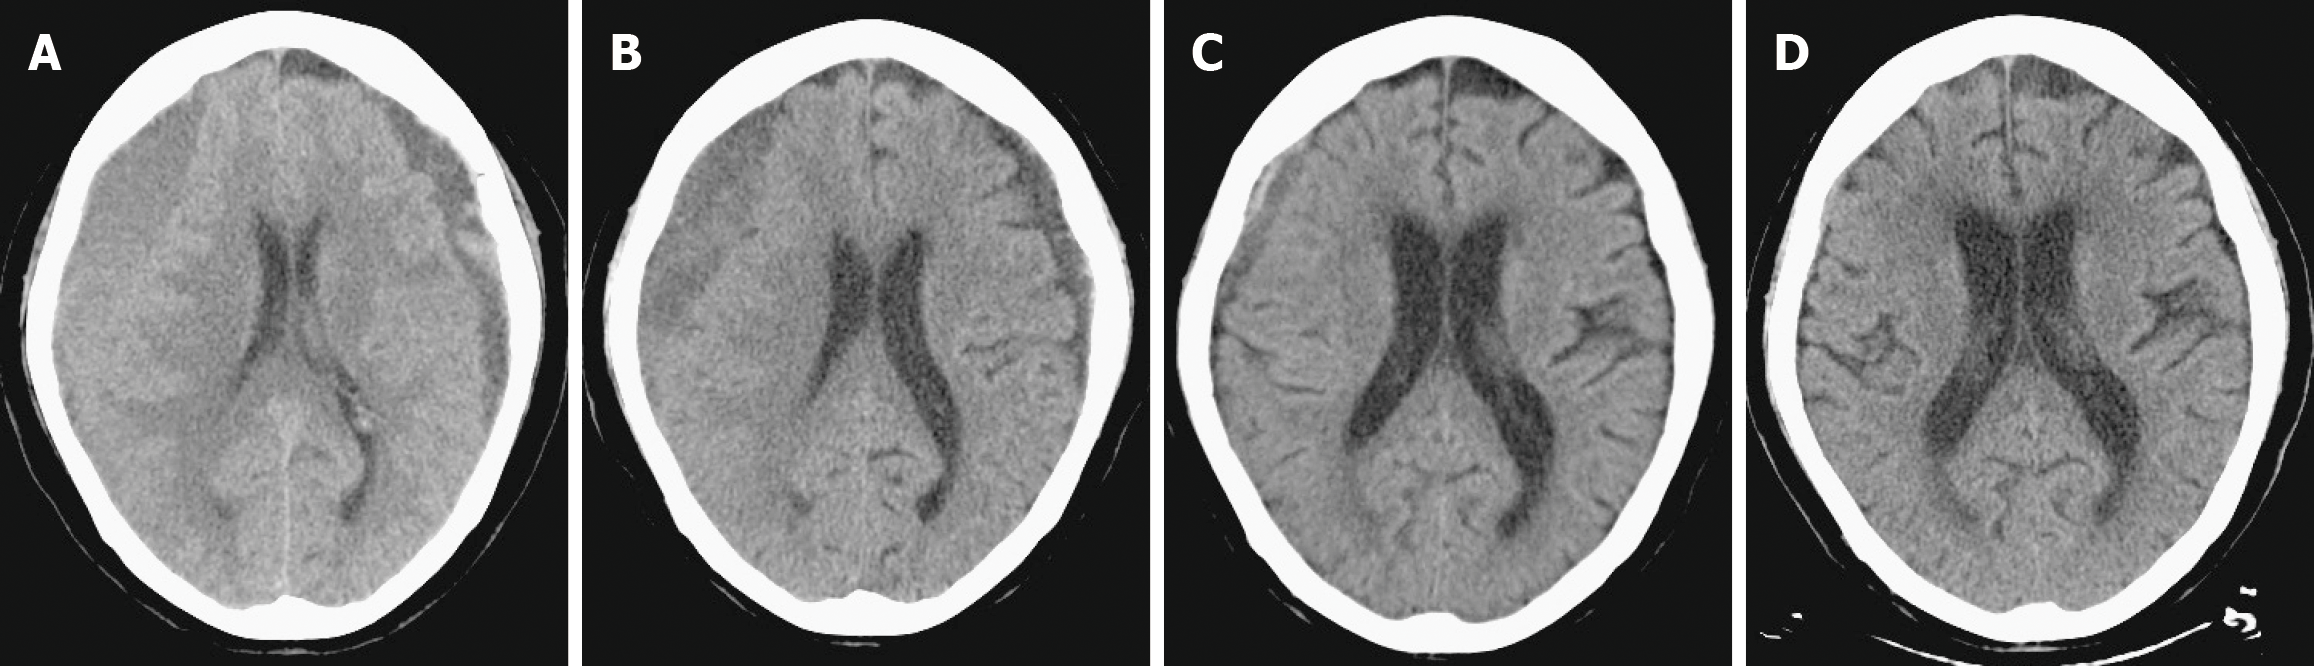

Follow-up CT scans at 1, 2, and 3 months post-procedure showed complete hematoma resolution and significant brain re-expansion (Figure 3). No procedure-related complications occurred.

In our case, bilateral hematomas resolved progressively following MMAE, with the larger right-sided gradational type requiring a longer clearance period than the smaller left-sided homogeneous collection (Figure 3). Established predictors of clearance include baseline hematoma volume, with larger collections resolving more slowly[13,19,22], and internal architecture, as homogeneous and laminar types resolve faster than trabecular or separated types[17,22]. Advanced age also correlates with delayed resolution, and brain re-expansion is often incomplete in those with baseline cerebral atrophy, underscoring the role of patient-related factors[17,22]. Conversely, the type of embolic material used has not been shown to significantly influence resolution rates[13,17,22].